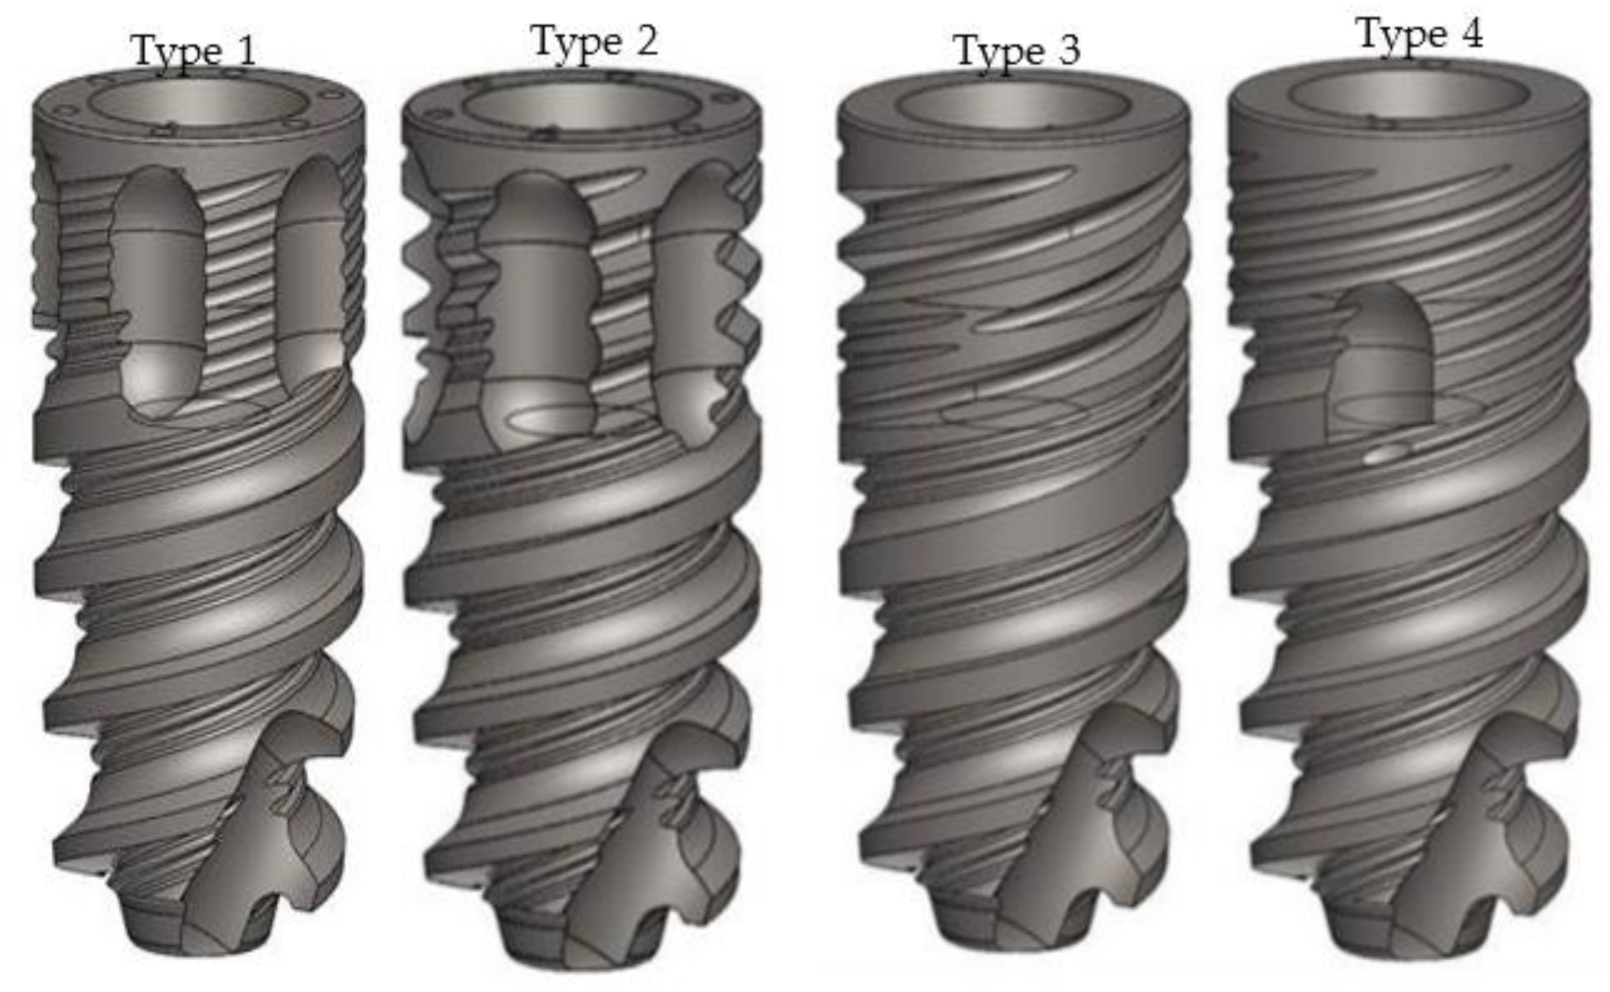

2. Materials and Methods